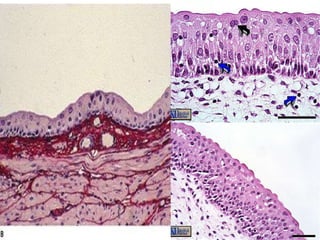

Pseudostratified Epithelium Structure Irregularly shaped cells with nuclei at different levels – appear stratified, but aren’t. All cells reach basement membrane Function Absorption and Secretion Goblet cells produce mucus Cilia (larger than microvilli) sweep mucus  Location Respiratory Linings & Reproductive tract

Stratified Squamous Epithelium Structure Many layers (usually cubodial/columnar at bottom and squamous at top) Function Protection Keratin (protein) is accumulated in older cells near the surface – waterproofs and toughens skin. Location Skin (keratinized), mouth & throat

Apical epithelial surfaces  These surfaces may possess specialized structures such as  microvilli ,  stereocilia , and  cilia .   1- Microvilli are finger like projections of epithelia (1µm length) extend into a lumen to increase the surface area - Glycocalyx is present on their surfaces - composed of actin filaments run longitudinally inserted in the terminal web - they constitute the brush and striated borders

2- Stereocilia are very long microvilli (not cilia) and are located in the epididymis and vas deferens of the male reproductive system 3- Cilia are actively motile processes (5-10 µm in length) extending from certain epithelia which propel substance along their surfaces They contain microtubules (axoneme) which arise from the basal bodies The axoneme consists of nine doublets microtubules uniformly spaced around two central microtubules The basal body is a cylindrical structure located at base of each cilium that consists of nine triplets microtubules arranged in radially like a pinwheel

Pseudostratified Epithelium StructureIrregularly shaped cells with nuclei at different levels – appear stratified, but aren’t. All cells reach basement membrane Function Absorption and Secretion Goblet cells produce mucus Cilia (larger than microvilli) sweep mucus Location Respiratory Linings & Reproductive tract

Stratified Squamous EpitheliumStructure Many layers (usually cubodial/columnar at bottom and squamous at top) Function Protection Keratin (protein) is accumulated in older cells near the surface – waterproofs and toughens skin. Location Skin (keratinized), mouth & throat

2- Stereocilia arevery long microvilli (not cilia) and are located in the epididymis and vas deferens of the male reproductive system 3- Cilia are actively motile processes (5-10 µm in length) extending from certain epithelia which propel substance along their surfaces They contain microtubules (axoneme) which arise from the basal bodies The axoneme consists of nine doublets microtubules uniformly spaced around two central microtubules The basal body is a cylindrical structure located at base of each cilium that consists of nine triplets microtubules arranged in radially like a pinwheel